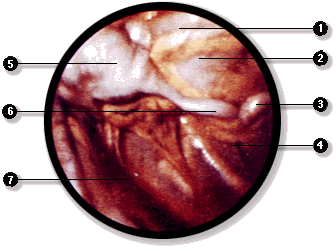

La cavidad peritoneal puede ser explorada directamente mediante la laparoscopía. En este examen se introduce un instrumento óptico, el laparoscopio, y se inyecta gas en la cavidad peritoneal para separa las hojas visceral y parietal del peritoneo. De esta manera es posible recorrer la cavidad e incluso realizar, bajo visión directa, ciertas intervenciones quirúrgicas que no requieren de un abordaje amplio de la cavidad abdominal.